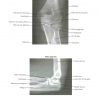

Atlas Giải Phẫu Chi Trên (Netter) | Bài giảng CĐHA

* Tác giả: Frank H. Netter v6 – 2016